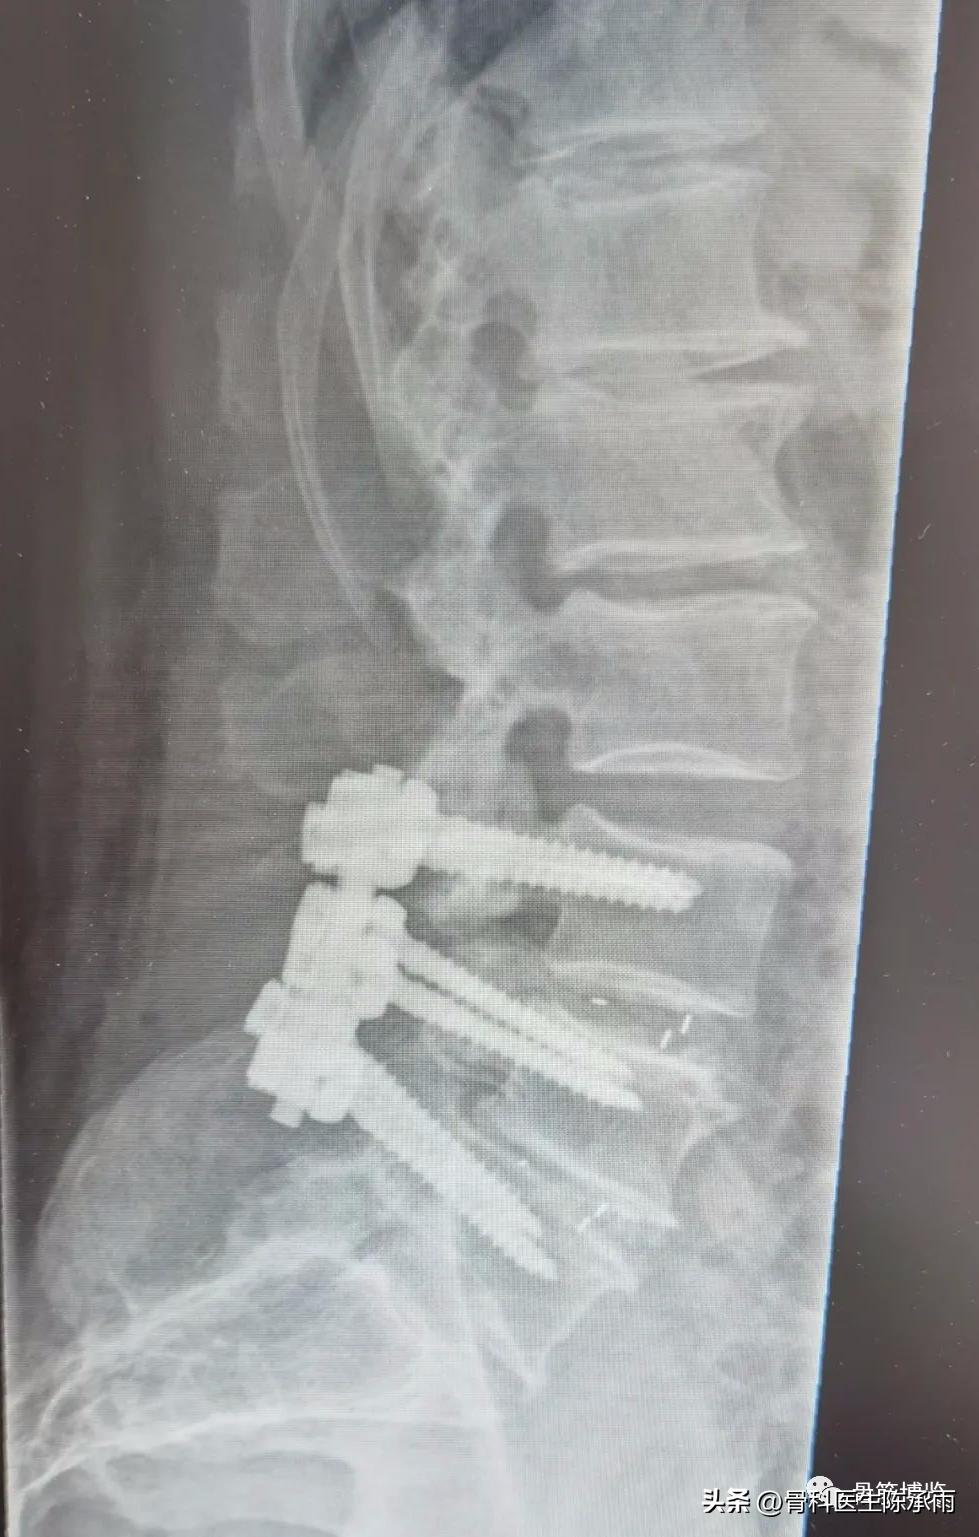

术中固定情况:后路全椎板减压,钉棒固定,两个间隙的椎间融合

术后影像